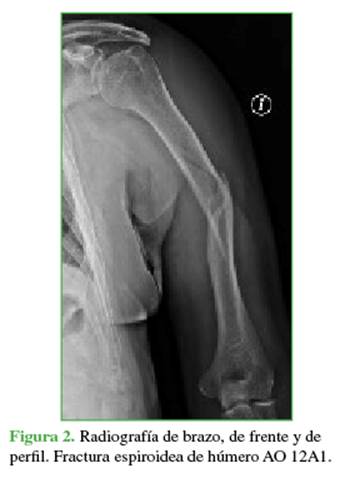

Las radiografías de húmero, de frente y de perfil mostraron una fractura diafisaria del húmero izquierdo (OTA/ AO 12A1; Figura 2).

El cuadro se interpretó como una lesión por tracción del nervio mediano tipo I-III de la clasificación de Sunderland, con afectación principal de las fibras correspondientes al nervio interóseo anterior. Se decidió el tratamiento quirúrgico de la fractura mediante osteosíntesis con un clavo endomedular, y se optó por una conducta expectante para la lesión neurológica.